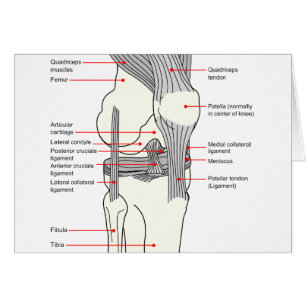

Illustration De L'Os Du Genou, Courbe

Prix de vente 6,48 $CA. Prix Initial 7,20 $CA.

Diagramme anatomique d'un joint humain du genou

Prix de vente 7,70 $CA. Prix Initial 8,55 $CA.

Carte Postale Douleur du genou121211

Prix2,64 $CA